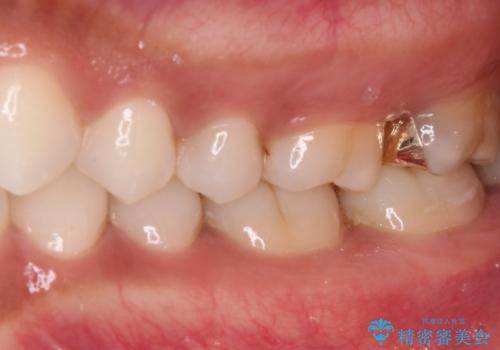

ゴールドインレーは銀歯のインレーやセラミックインレーと比べ、「技工操作の精度が高く、適合が著しく良い」というメリットがあります。特に上の奥歯は歯科医師の操作が行いにくいため、「適合の良さ」は再治療のリスクを防ぐ上でとても重要な要素となります。

上の奥歯は金属色が見えることもないため、審美的な問題は全くありません。

咬み心地はとても良好で、全く違和感がなく、患者様には大変満足していただきました。